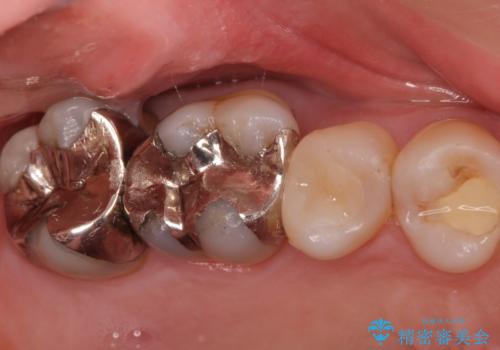

奥歯がしみて痛い

- 冷たいものがしみて飲み物が飲めないとの事で来院。

歯肉が退縮していたので歯周外科手術(歯茎の移植手術)か被せ物で覆う(歯肉退縮しているところまで覆う)の提案をしたところ被せ物がいいとのことでしたので

被せ物の治療のご案内になりました。

適合の良い被せ物が入りました。

冷たいものがしみなくなり大変満足してもらいました。

一つ前の歯も後に染みてくる可能性があるとの事で被せ物をするか検討中です。